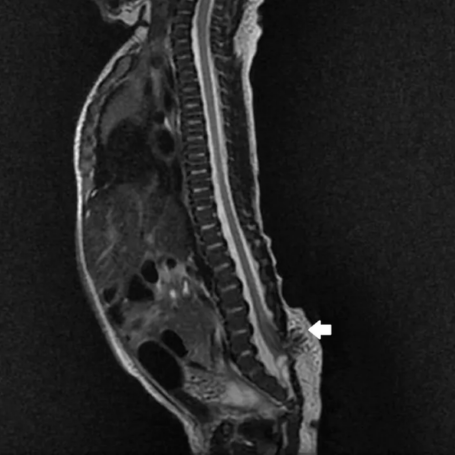

Diagnóstico: Se basa en la evaluación clínica de síntomas como dolor lumbar, debilidad en piernas o alteraciones urinarias. Se confirma con resonancia magnética (RM), que permite visualizar la fijación anormal de la médula.